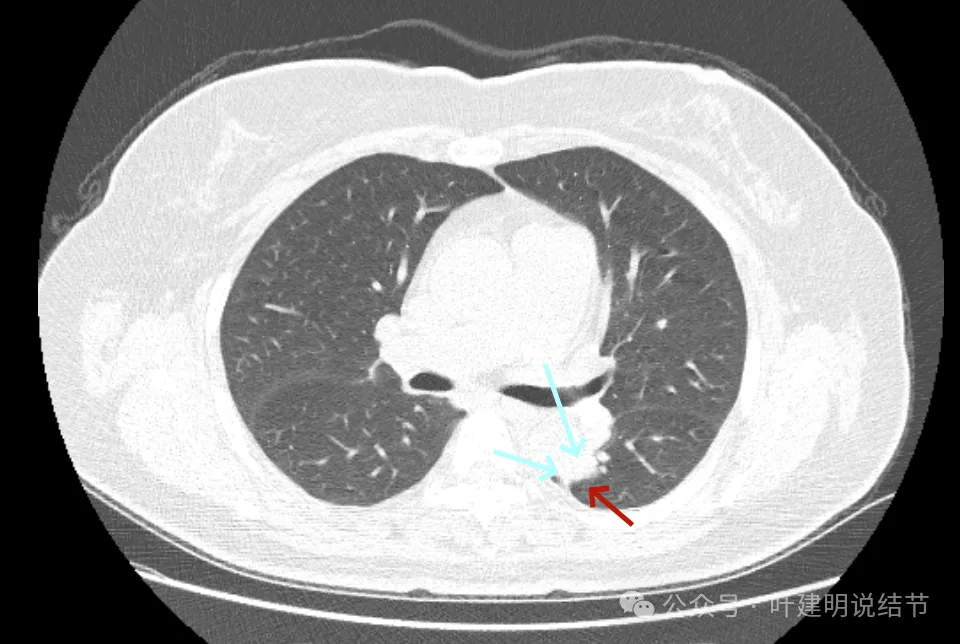

再看2022年的影像:

病灶磨玻璃密度,天蓝色这处密度高的条索状,紫色这处毛刺细长,病灶此层没有膨胀性,更像慢性炎伴纤维增生的样子。

密度不均,有实性成分了,表面分叶,但膨胀性仍不强。

基本实性密度,边缘较为平直,胸膜牵拉不显著。

病灶瘤肺边界稍显模糊,但与2019年时比,邻近胸膜增厚似乎不如之前明显。

从3年对比来看,由于没有吸收好转,也说不上显著展,虽恶性概率较前有所增加,但慢性炎或肉芽肿性炎仍可能的。谨慎随访也是可行的。当然现灶在边缘,若定要明确,微创手术也是可行的。或者查下PET,但这种几乎进展不明显的病灶,估计有代谢增高,一般也是轻度增高,仍不能完全明确性质的。